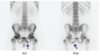

Erdheim Chester disease non Langerhans histiocytosis --> fibrosis and osteosclerosis